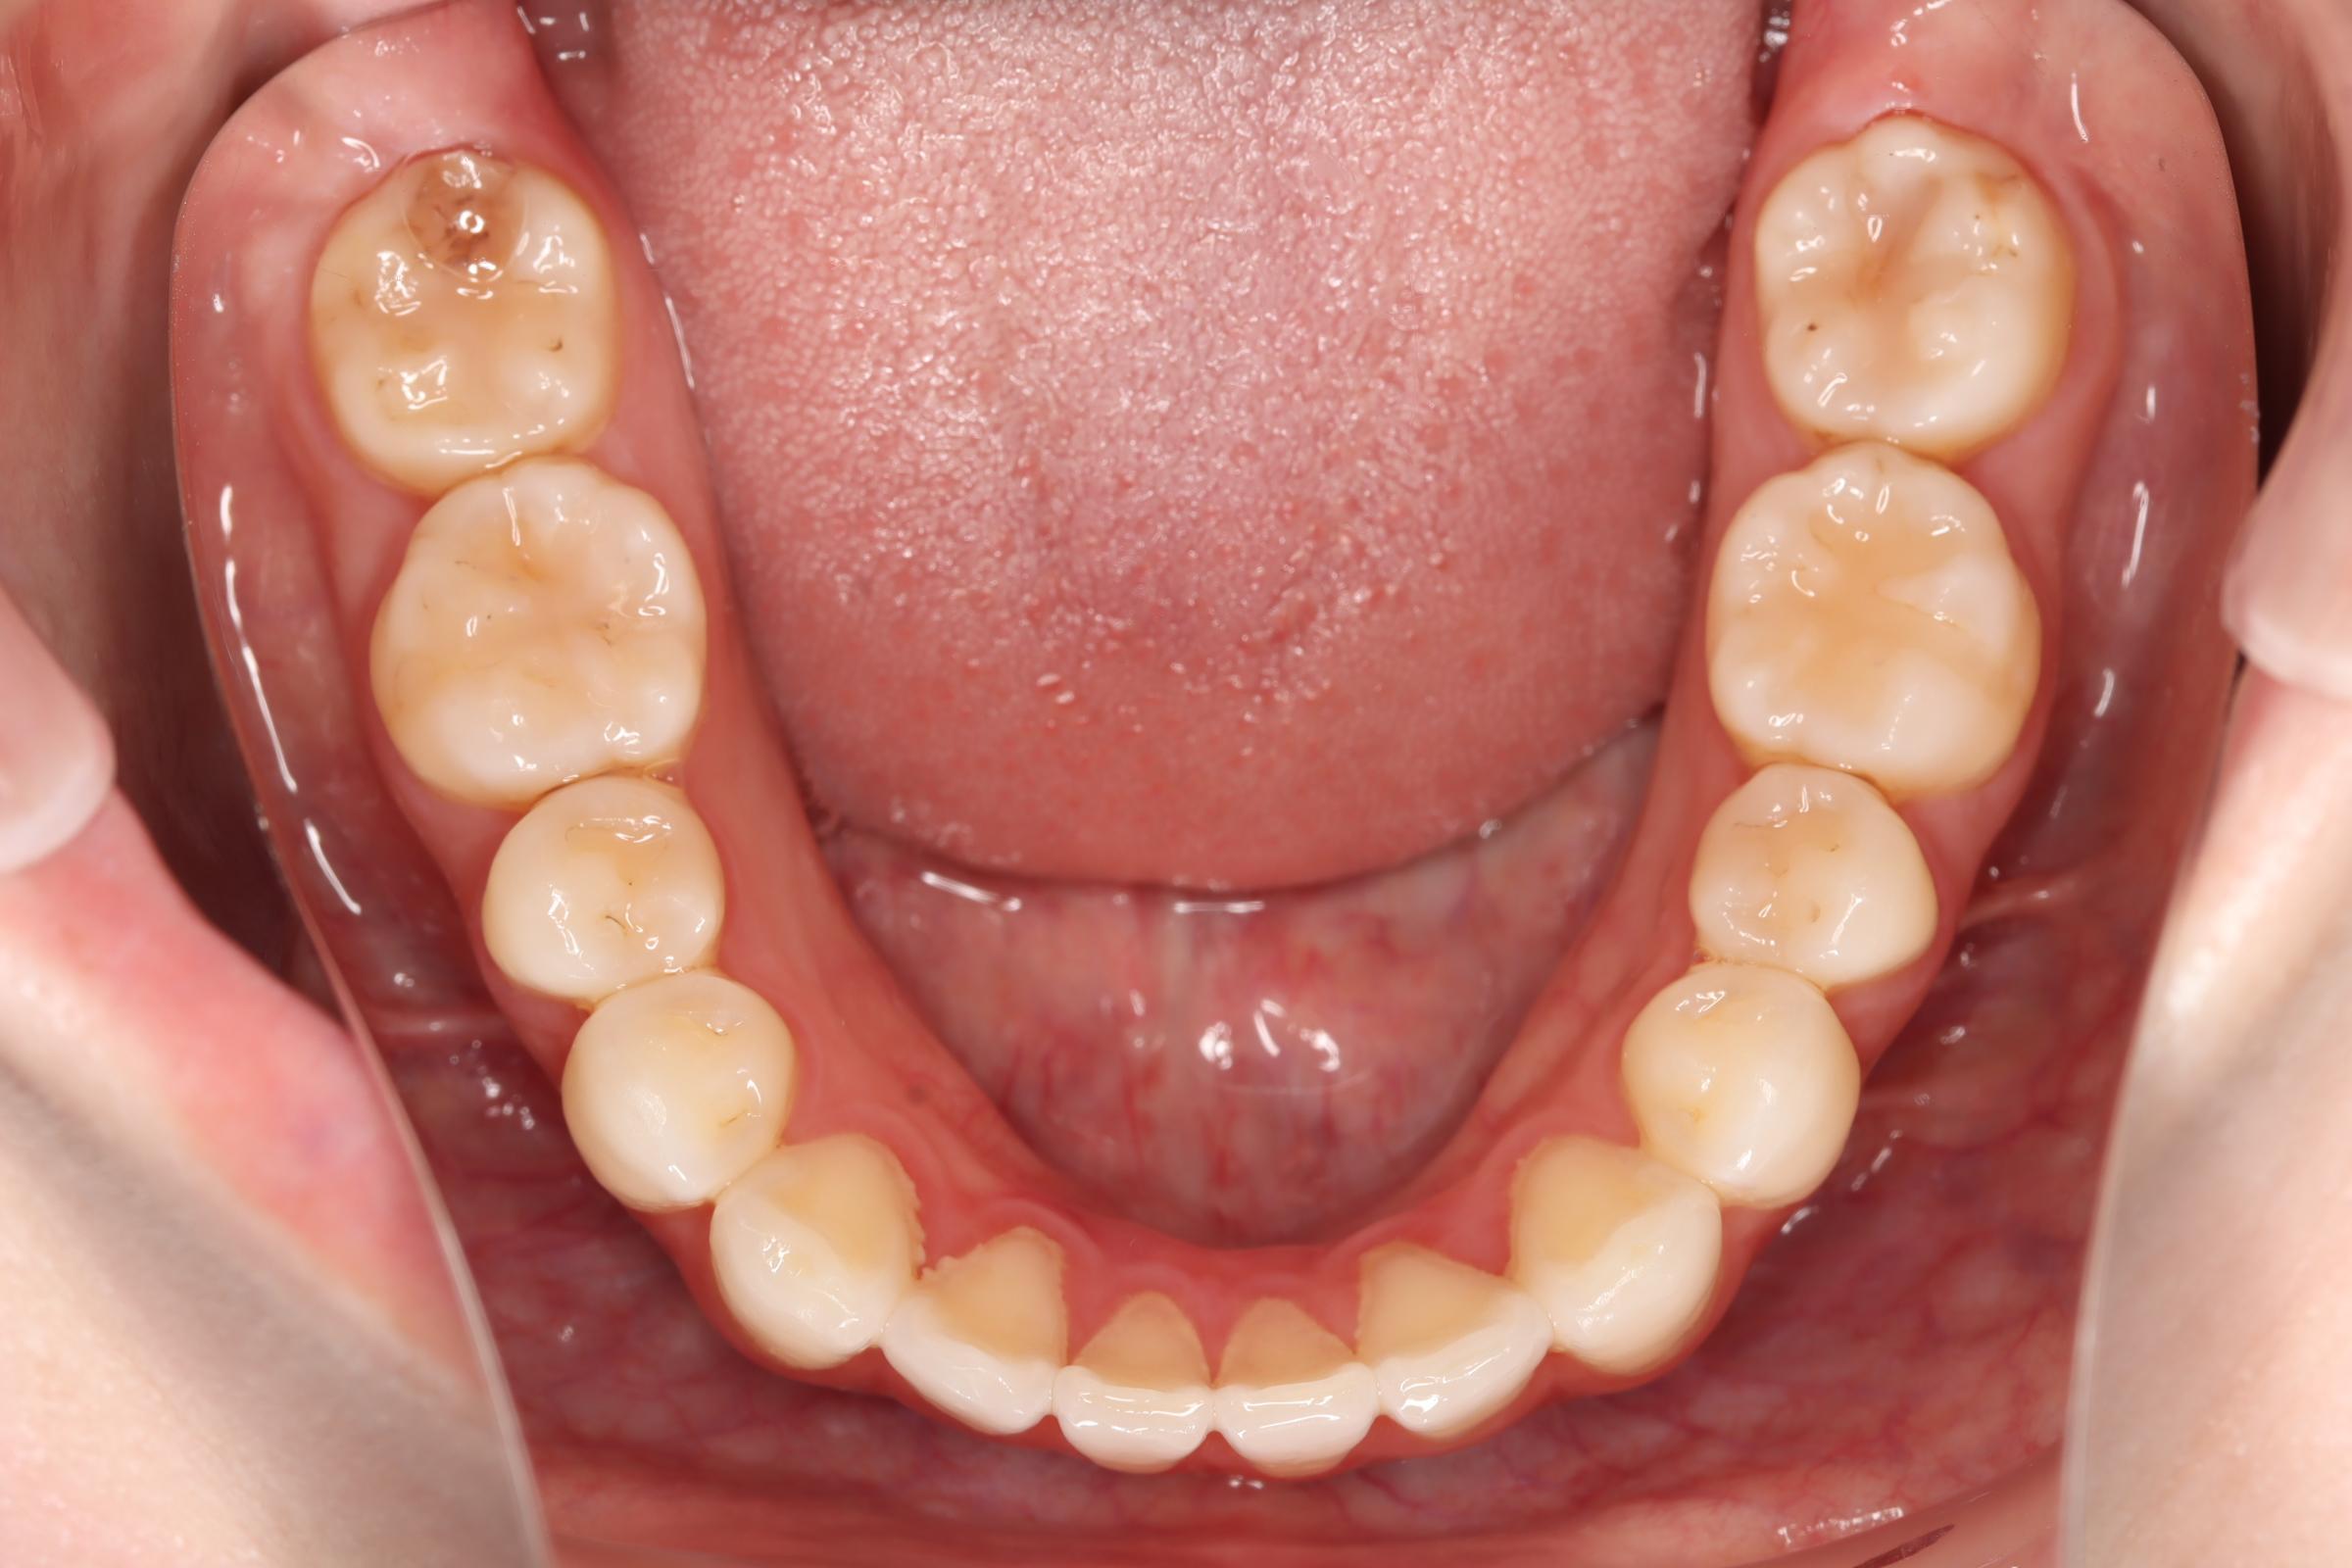

口腔内の変化

![]() | ![]() | ![]() |

| ↓ | ↓ | ↓ |

| 治療前 | 骨格的には受け口の患者さんですが、上顎前歯の唇側傾斜が大きく、患者さんとしては出っ歯だと思われていたパターンです。 元々口元の突出感はほとんどなかったため、歯を抜かずに上下顎ともに歯列を後方に移動させることにより主訴を改善させることとしました。 |